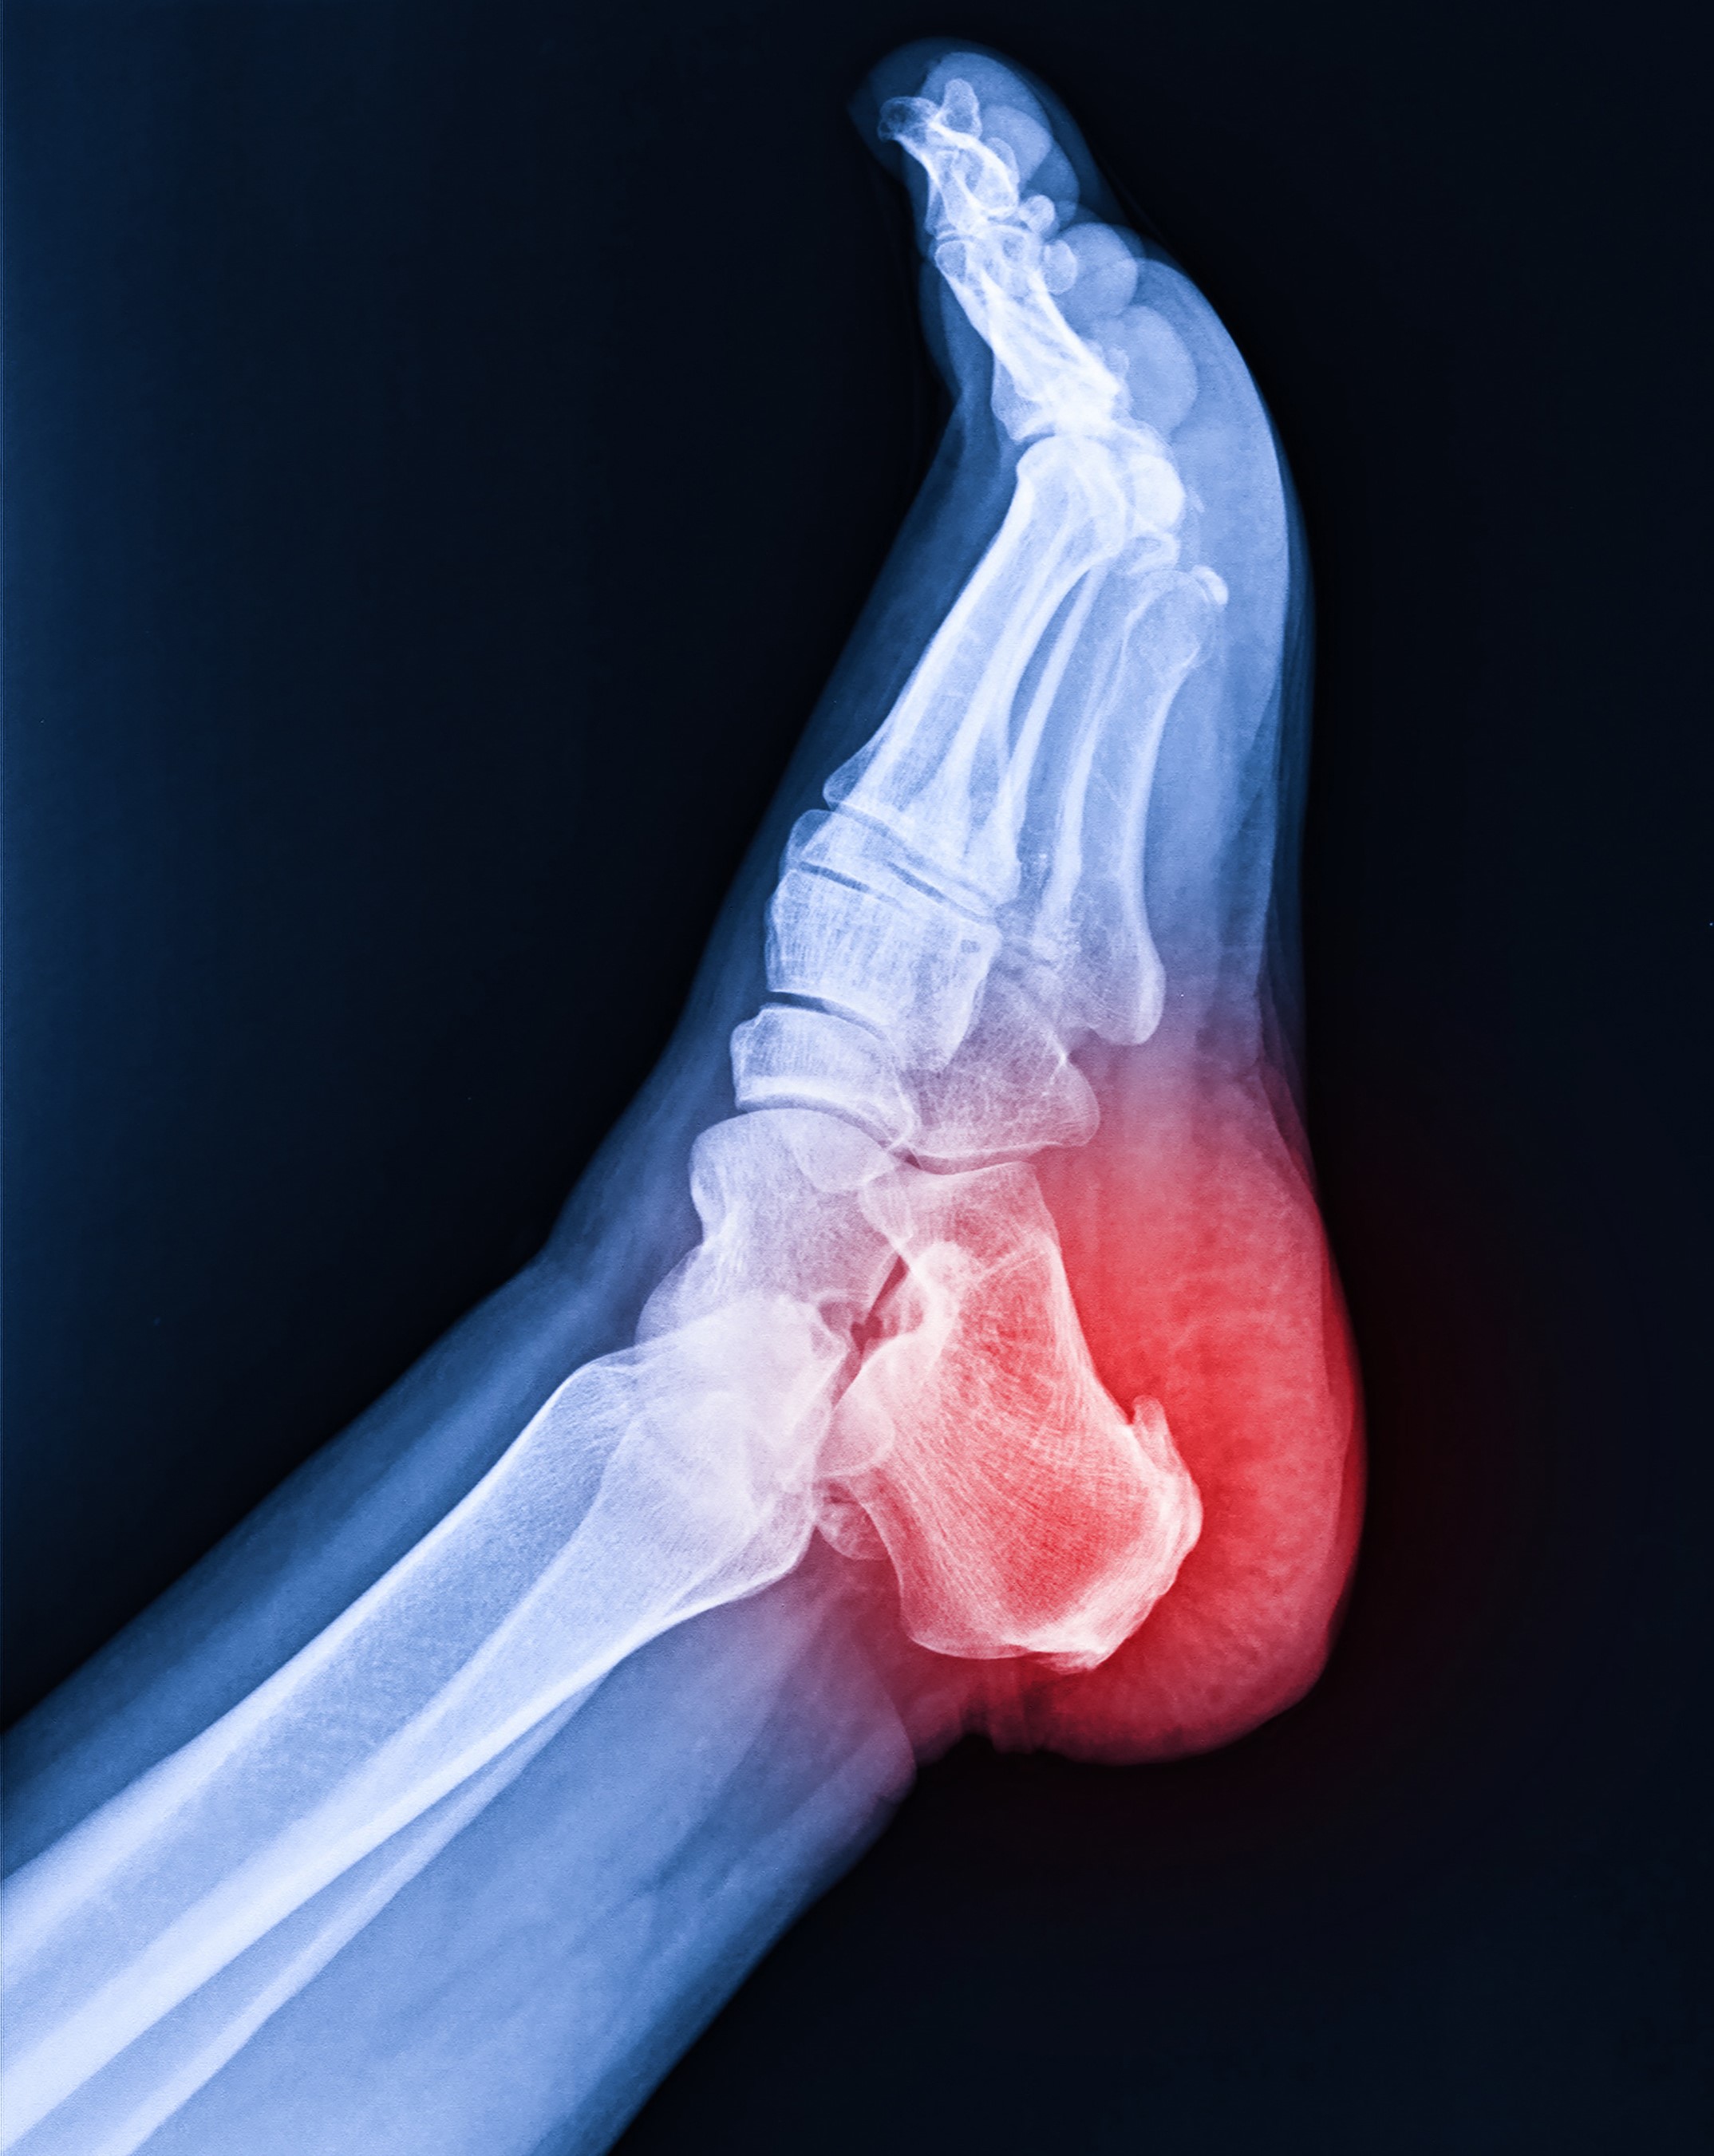

Plantar Fascia: The Key Player in Human Movement

The plantar fascia stands out as one of the strongest and most vital components within the fascial system. It plays a crucial role in managing ground reaction forces (GRF), providing a solid foundation for both static and dynamic human movement. Beyond its role in supporting movement, the plantar fascia transmits initial somatosensory input to the central nervous system (CNS) and fascial network. Additionally, it generates propulsive forces and efficiently conveys them throughout the entire fascial system.

Originating from the plantar calcaneal tuberosity, the plantar fascia extends through the medial longitudinal arch and inserts extensively across the proximal phalangeal bases, connecting with the plantar plate and plantar skin through fascial extensions. This robust structure is richly innervated by the four types of mechanoreceptors (MCRs), endowing it with crucial proprioceptive and motor coordination input.

Phylogenetically, the plantar fascia shares similarities with the tendo Achilles. It consists of two layers—the superficial and deep layers—divided into three bands: medial, central, and lateral, with connections to intrinsic foot musculature. The thickness of the plantar fascia remains fairly constant at approximately 3-4mm with age, but it may thicken in individuals with diabetes or tighten in cases of Plantar Fasciitis, often associated with increased tension in the Achilles tendon.

Plantar fascia pain may not solely originate from the foot; it can also be referred from the spine or be influenced by weak gluteal muscles, tensor fascia lata, or quadriceps' ability to respond to ground reaction forces. The plantar fascia demonstrates continuity with the fascia of the lower limb, trunk, neck, head, and internal organs through the visceral fascia. This interconnectedness allows for the fascial chain networks, commonly referred to as "from toe to tongue."

As the "first responder" to ground reaction forces, the plantar fascia stages the transmission of neural impulses and interprets mechanical signals. These responses trigger subsequent CNS reactions and motor execution, orchestrating coordination, balance, and movements. This seamless interplay between the plantar fascia, nervous system, and musculature is often described as "biotensegrity," reflecting the importance of the fascial network's integrity in supporting our body's overall function and movement abilities.